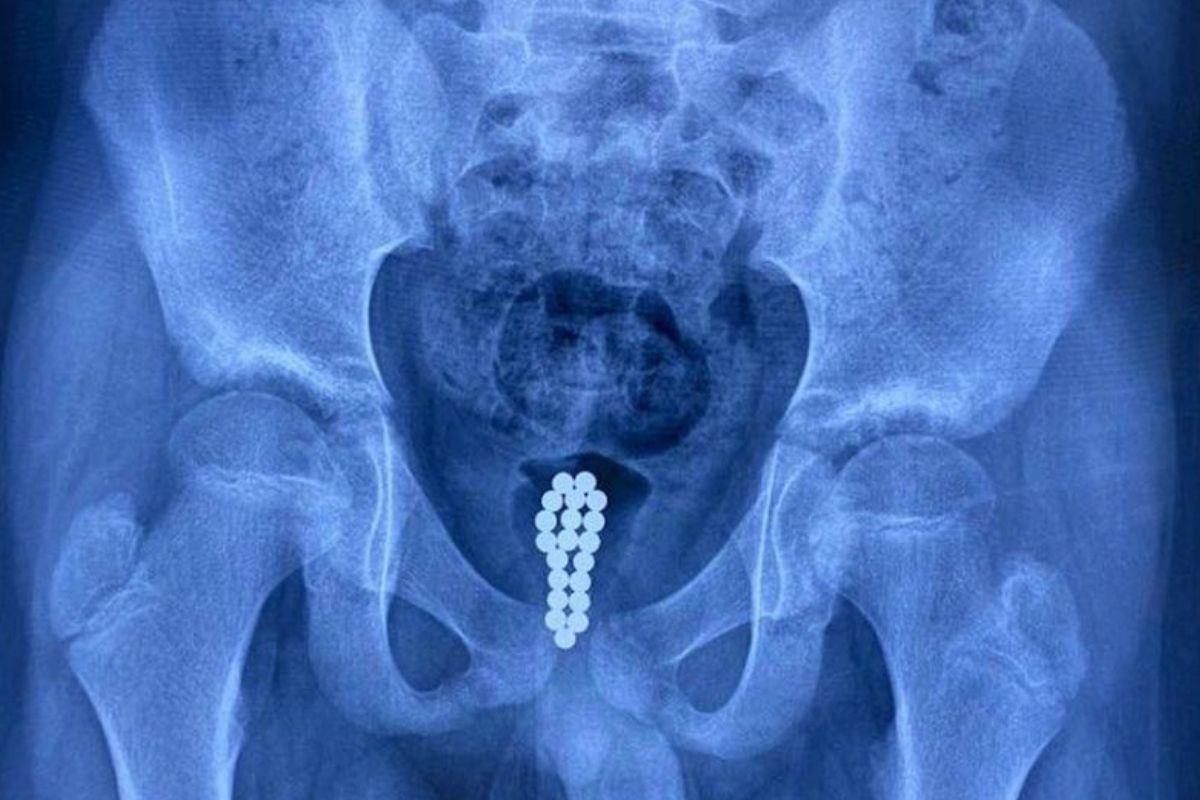

Li Honghui, urologista chefe do Hospital Infantil Dongguan, ficou chocado quando descobriu o que havia acontecido com o menino. Após passar por uma cirurgia de emergência na bexiga, o médico explicou que o que causou a inflamação foram as “Buckyballs”, pois possuem uma espécie de imã.

Ao entraram em contato com o órgão da criança, as bolas metálicas foram enferrujando. “Mas como não conseguimos remover uma série de 20 esferas através de uma cistoscopia, optamos por uma cirurgia minimamente invasiva”, explicou.